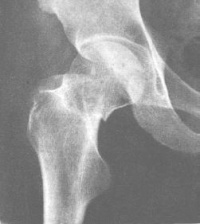

股骨颈骨折X光

按股骨颈骨折部的形态分为嵌入型和错位型骨折。这两型股骨颈骨折的骨折线可表现为致密线和/或透亮线。致密骨折线表示两骨折端的骨小梁有重叠嵌插,而透亮骨折线则意味着两骨折端有分离。

嵌入型股骨颈骨折无明显错位,通常股骨颈可见模糊的致密骨折线,局部骨小梁中断,局部骨皮质出现小的成角或凹陷,股骨干的外旋畸形小明显。此型骨折属较稳定性骨折。由于骨折发生时外力作用的不同,股骨头可发生不同程度的内收、外旋。前倾或后倾的成角畸形。如出现嵌入端成角畸形较明显,或骨折线的斜度较大、骨折端部分有分离,或股骨干外旋明显时,提示骨折不稳定。

错位型股骨颈骨折较常见,亦称为内收型股骨颈骨折。两折端出现旋转和错位。股骨头向后倾骨折端向前成角,股骨干外旋向上错位,骨折线分离明显。

另外,接骨折部位又可分型为:头下型:骨折线位于头颈交界处;经颈型:骨折线位于股骨颈的中段;基底型:骨折线位于股骨颈底部,大部分位于关节囊外;头颈型:骨折线上端在头下,下端在股骨颈的中部,此型骨折近端的血供不好,不易愈合。